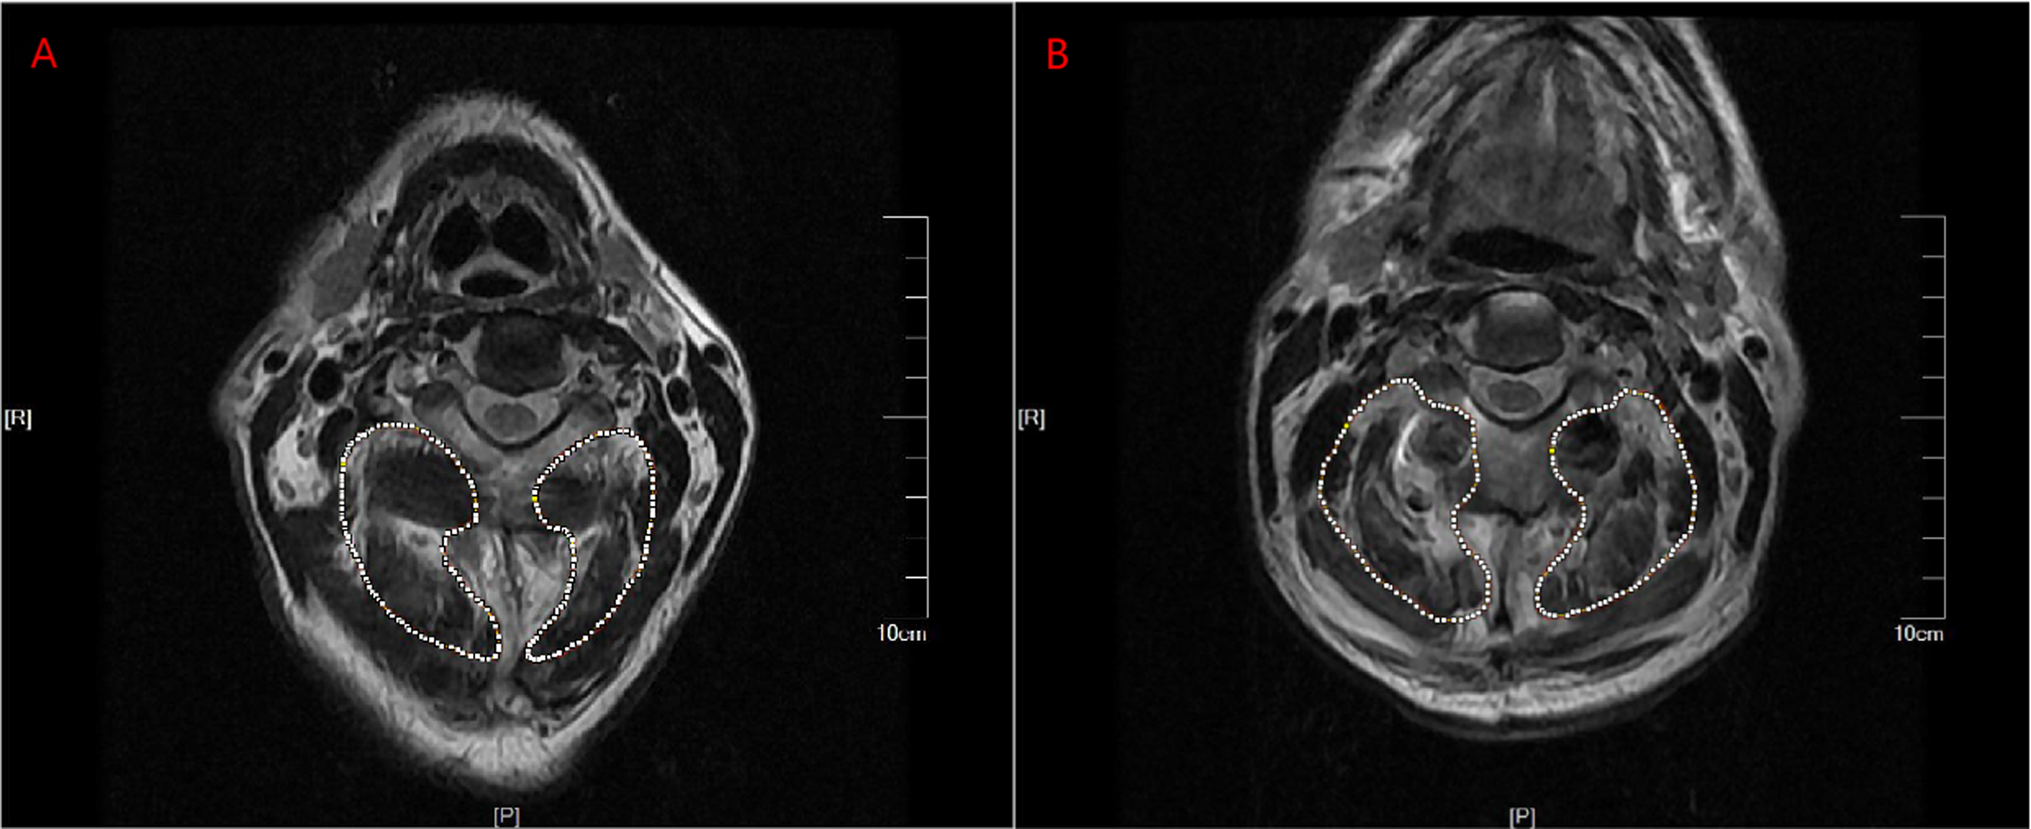

Fig. 2

Schematic representation of preoperative and postoperative measurements on the cross-sectional area (CSA) of the paravertebral tissue. The CSA of the paravertebral tissue was defined as the area circled by the dotted line. The measurement range of CSA after operation was consistent with that before operation. The postoperative CSA of the paraspinal tissues at the level of C2 spinous process on both sides (the area circled by dotted lines) (B) was significantly larger than the preoperative CSA (A).